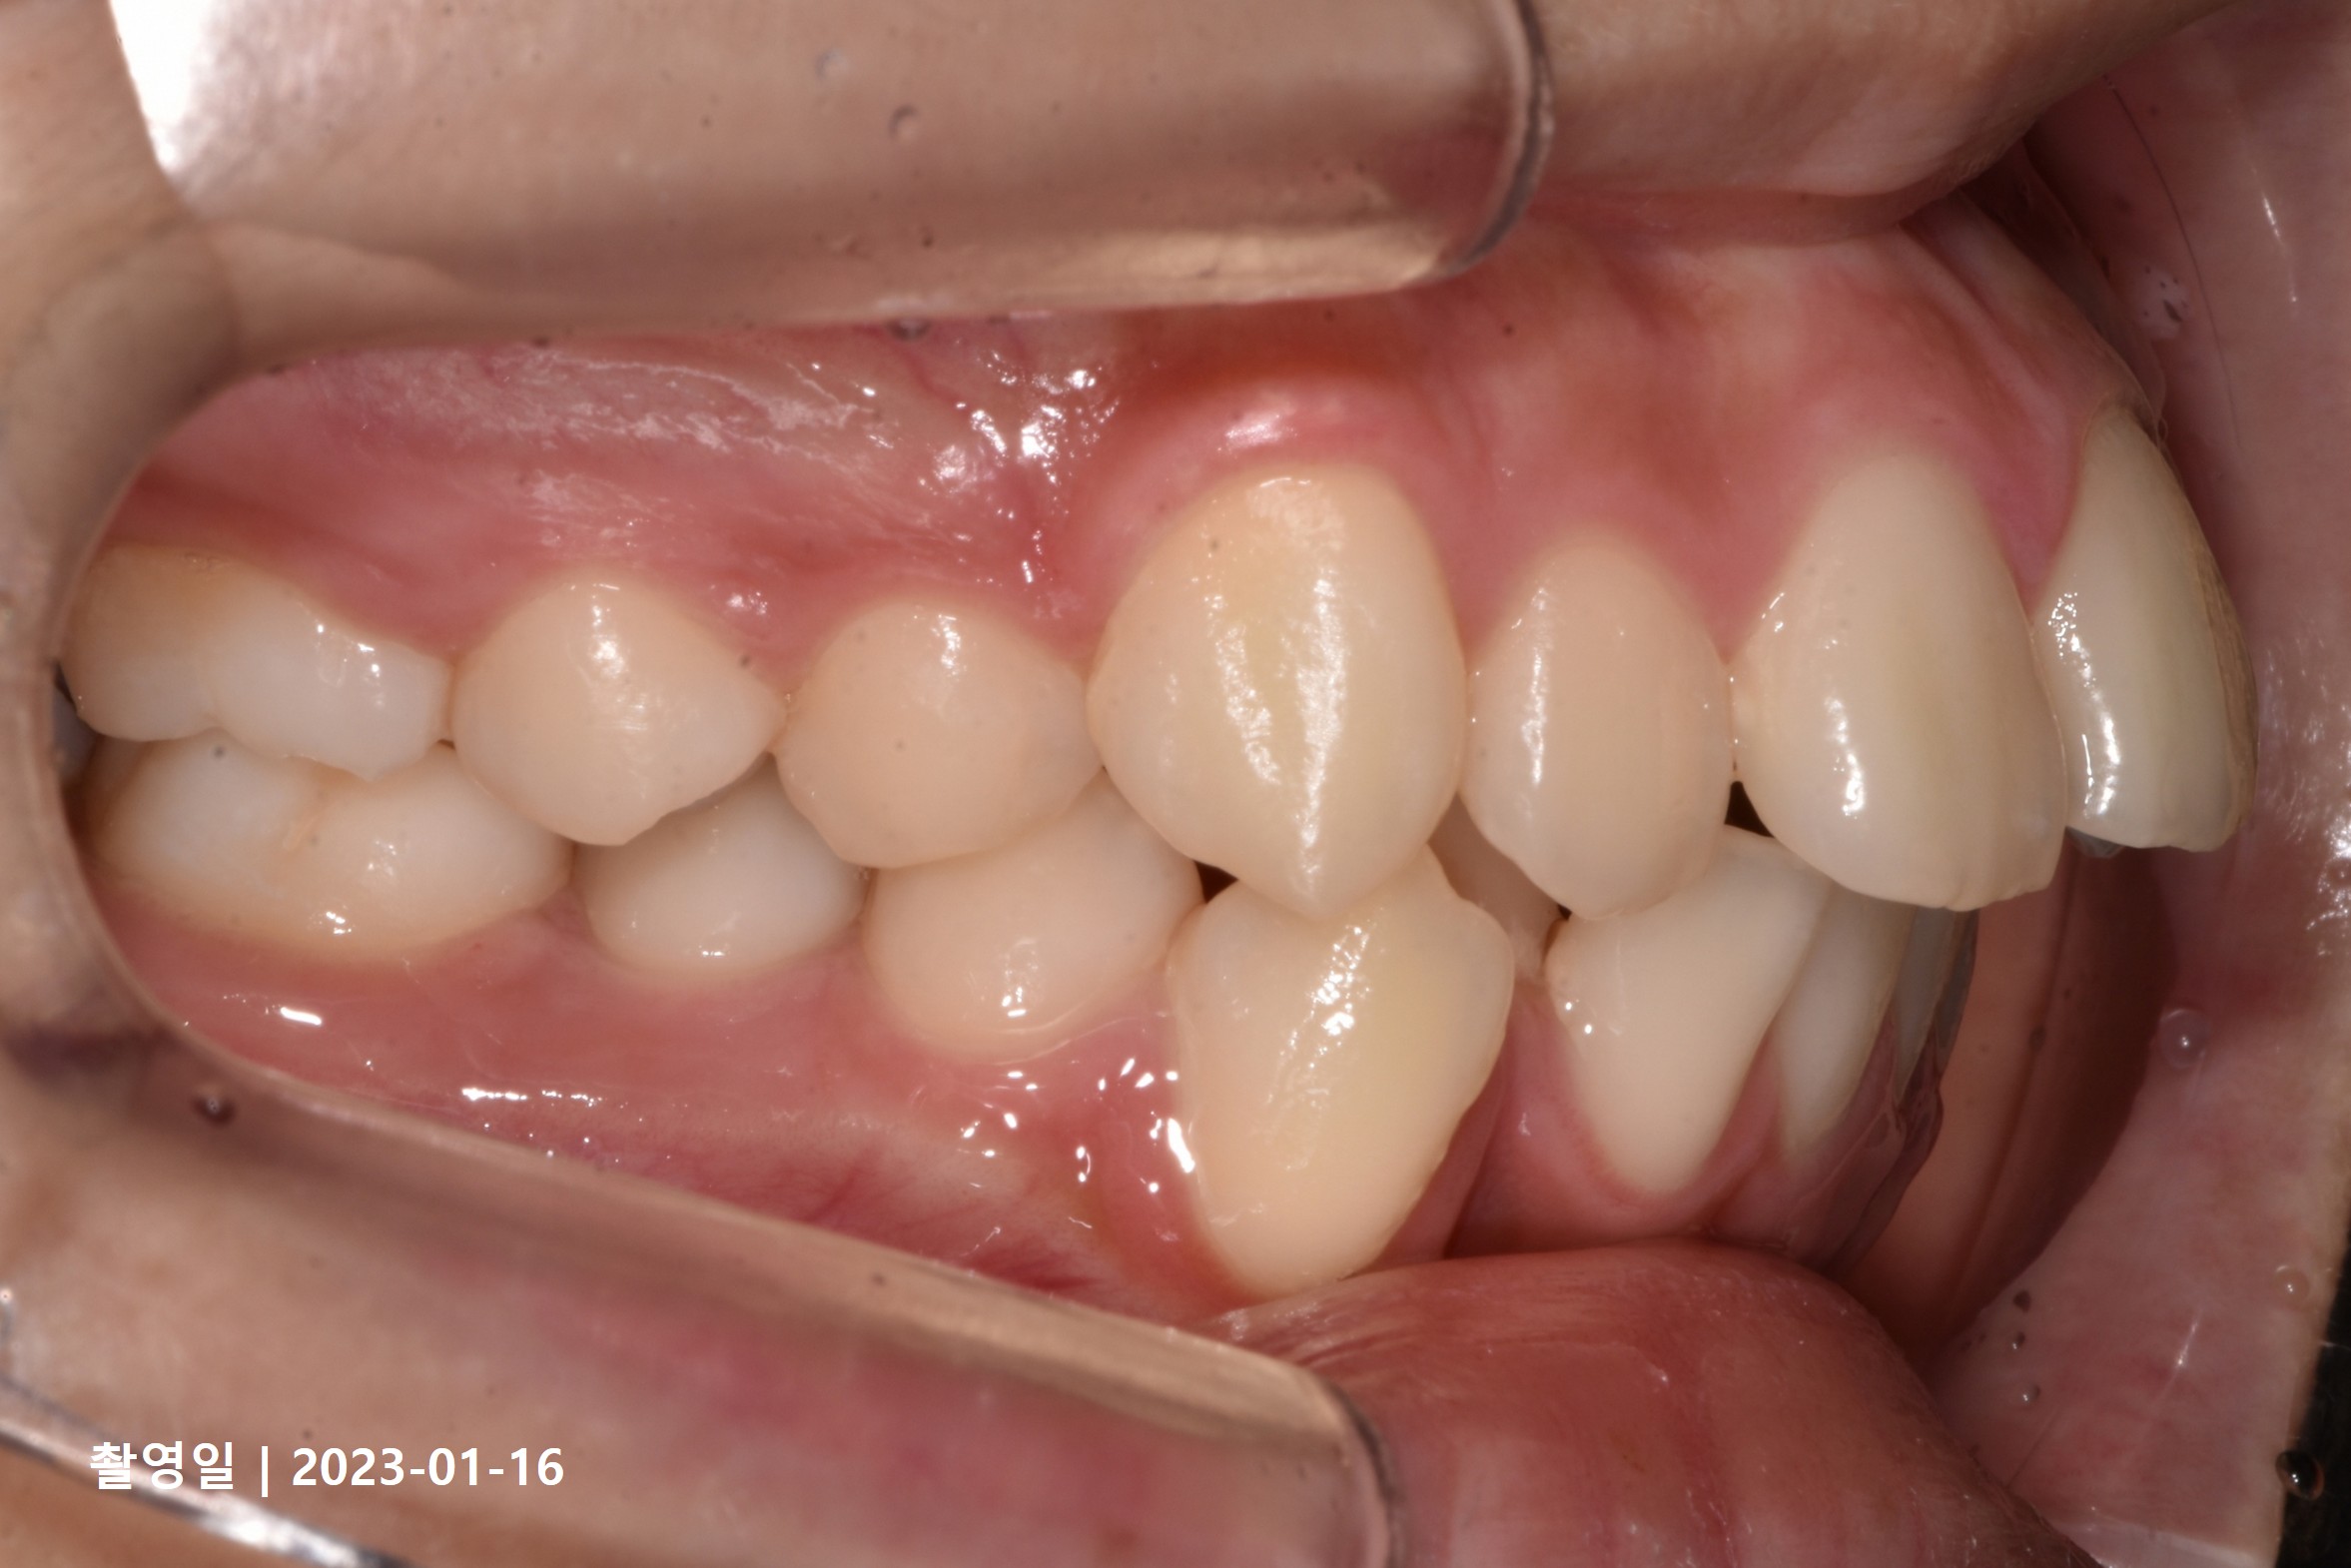

Case 4

- 19세 여성

- 상하악소구치 발치

- 치료기간 2년 8개월

치료 전

치료 후